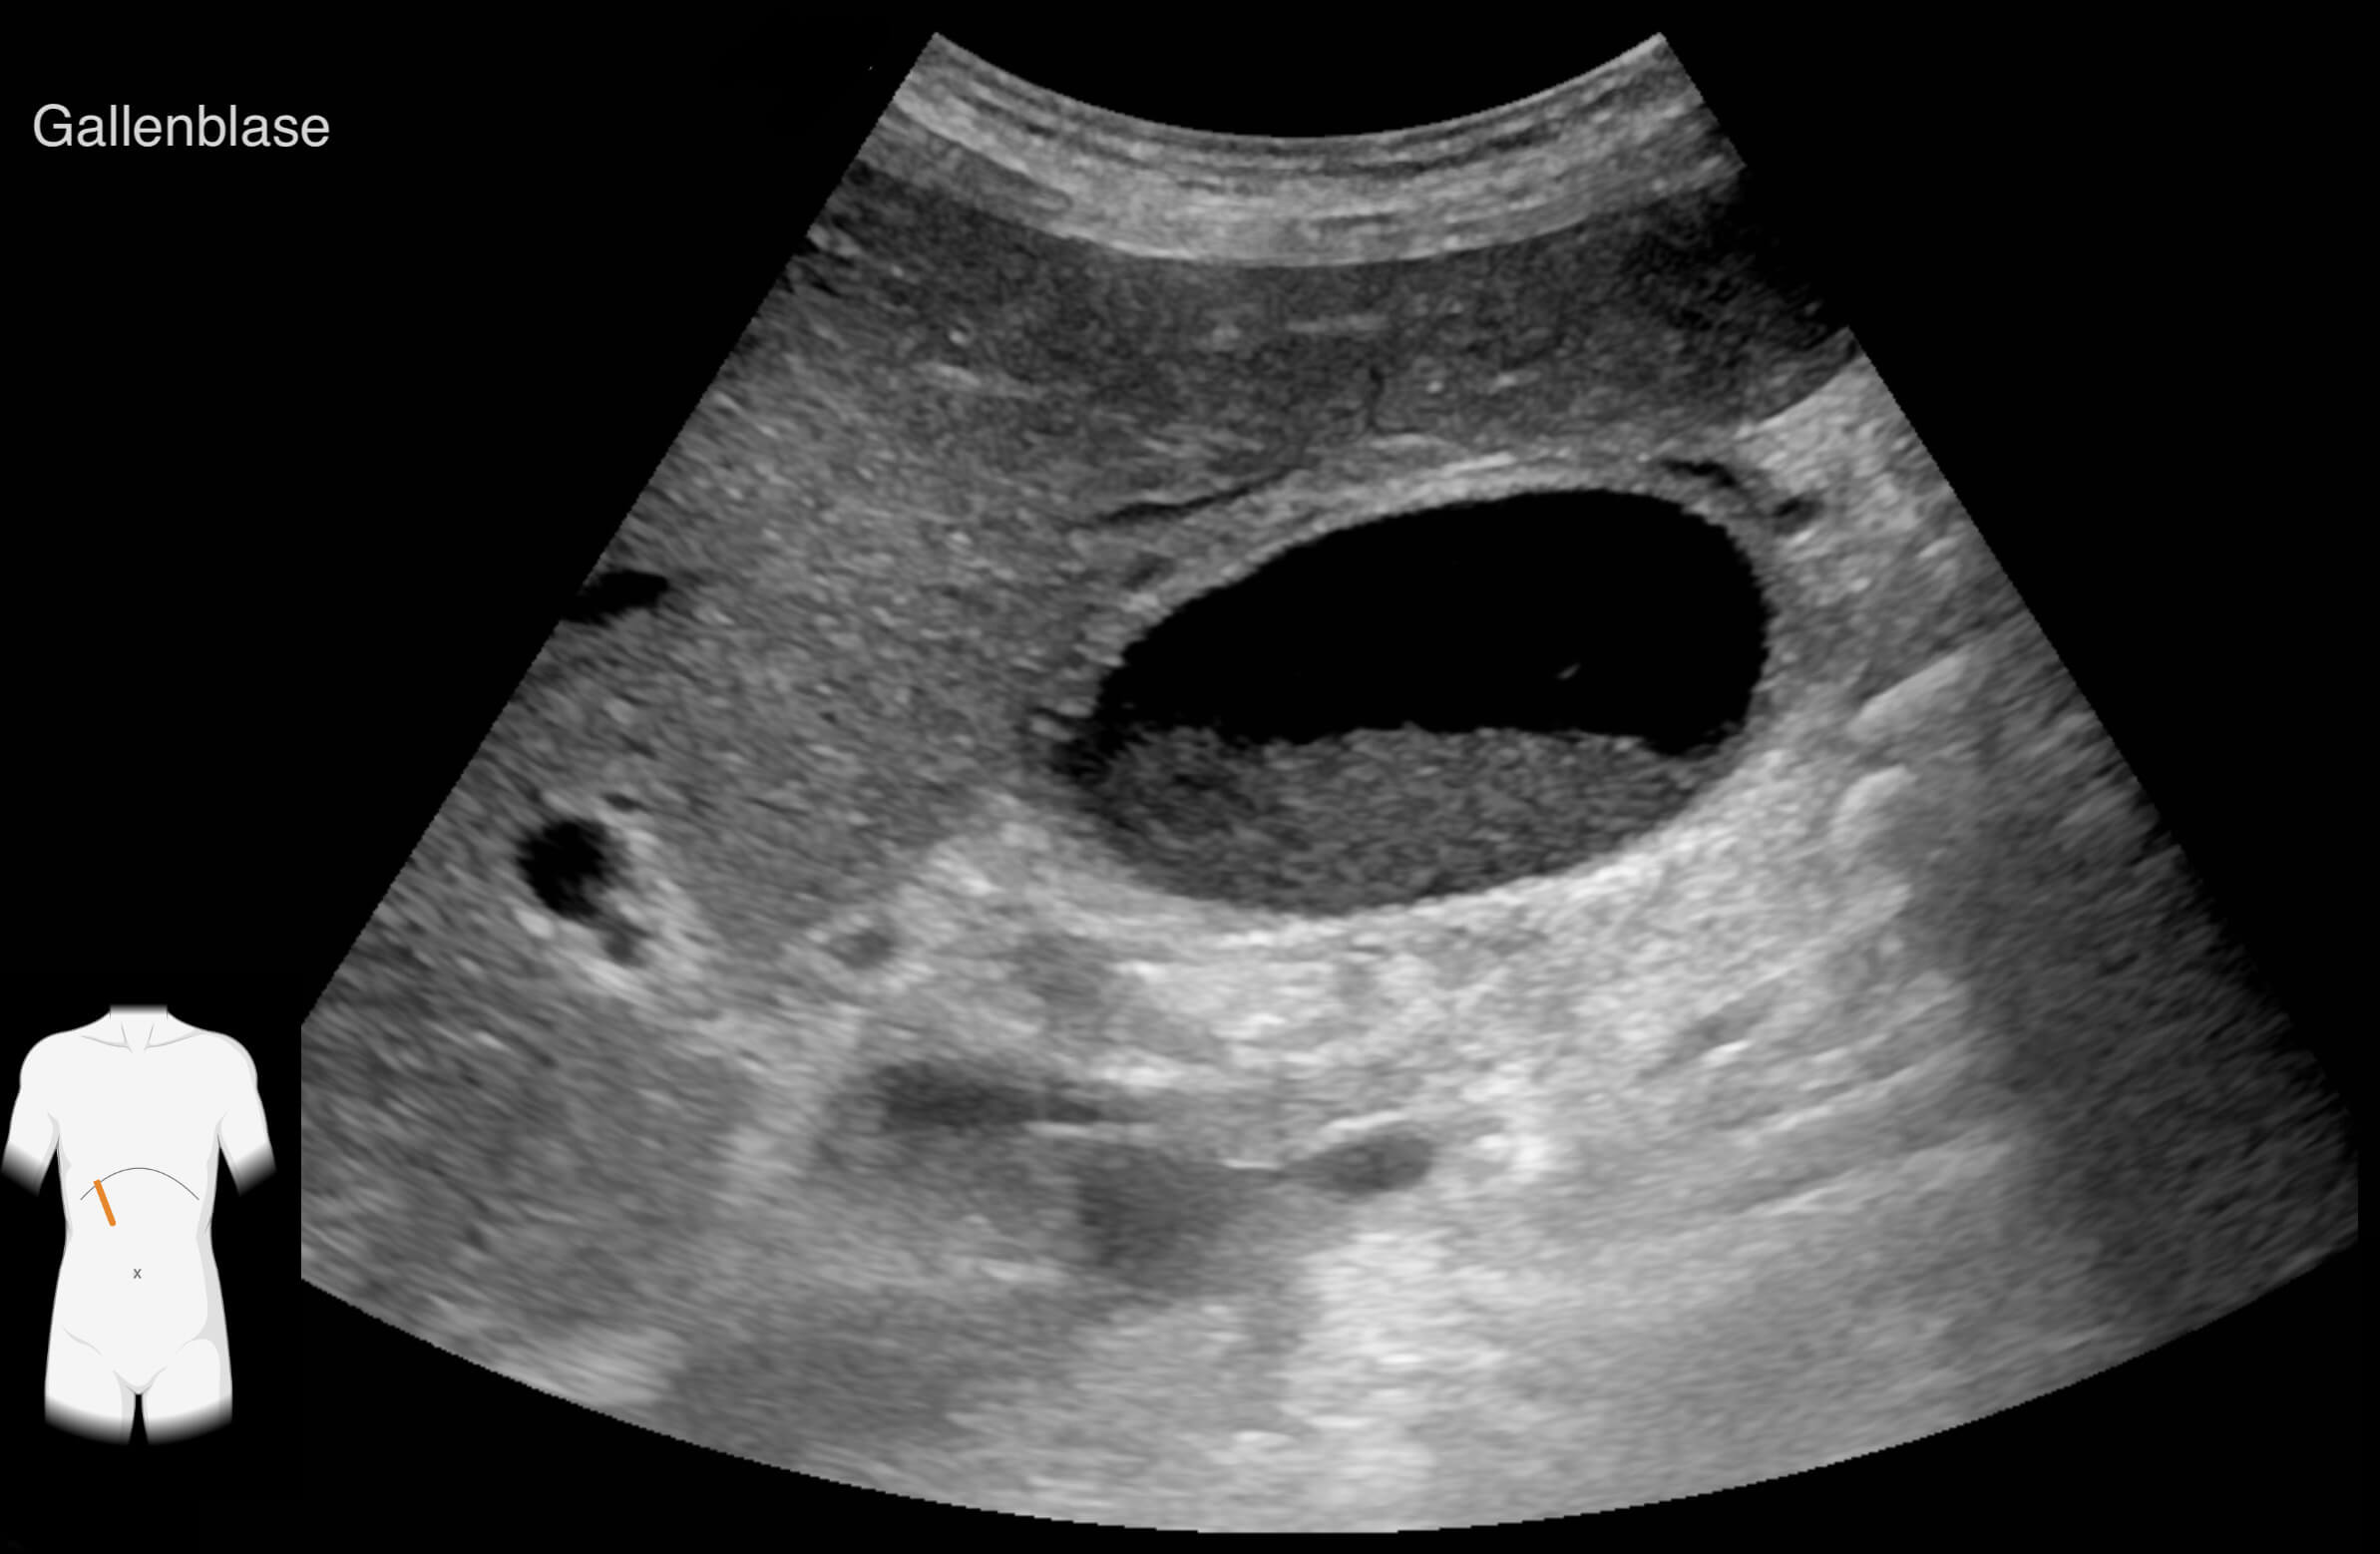

Die Ergebnisse der durchgeführten Untersuchungen kannst du dir hier anschauen:

Die Befunde geben eindeutige Hinweise auf die Erkrankung von Frau Lorenz. Wie bewertest du die Ergebnisse?